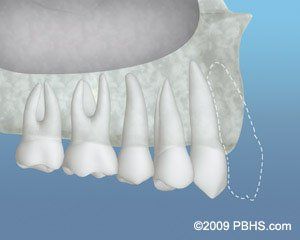

About Gum Recession

When gingival recession occurs, the body loses a natural defense against both bacterial penetration and trauma. Gum rebuilding using grafting methods is an alternative when gum recession is a problem.

When there is only a minor recession, some good gingiva often stays and protects the tooth, so there is no need for therapy other than changing home care practices.

However, the first line of defense against bacterial penetration is lost when the recession reaches the mucosa.

Additionally, gum recession often results in root sensitivity to warm and cold foods as well as an unsightly appearance of gum

and tooth.

When significant, gum recession may predispose to worsen recession and expose the root surface, which is softer than enamel, leading to root caries and root gouging.